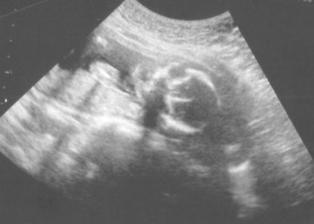

Kontrola u Dr. 7.4. dopadla dobře, srdíčko tluče, miminko jsem viděla.

Další UTZ nás čeká 5.5. a dostaneme konečně i obrázek 🙂

Kontrola proběhla v pořádku rosteme tak jak máme. Mimíska jsme s tatínkem viděli a konečně si i fotečku odnesli. 2.6. jdete na odběry kvůli screeningovým testům a pak hned 7.6. pro výsledky.